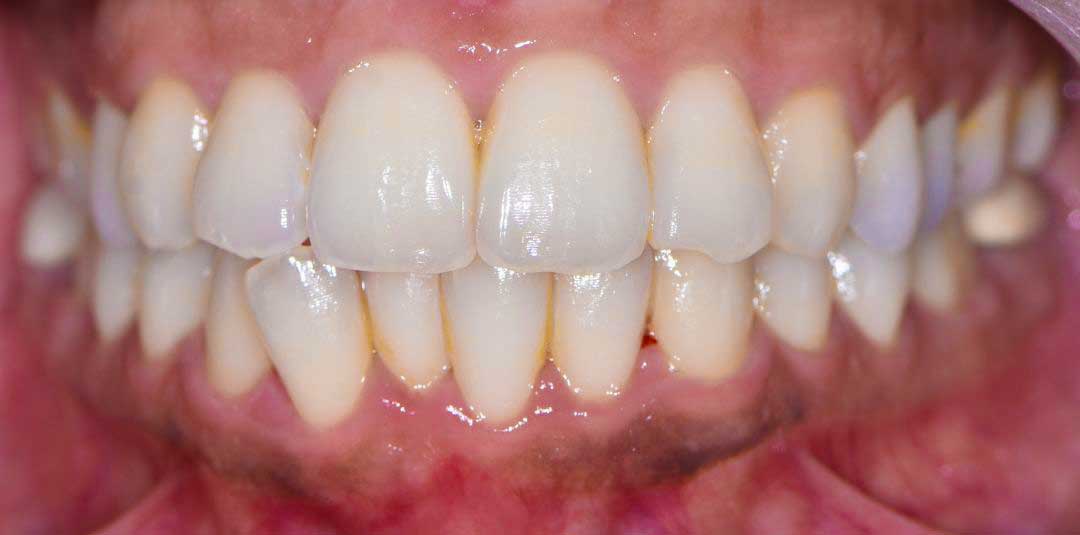

Beautiful Smiles

by Dr. Paolo Bellini